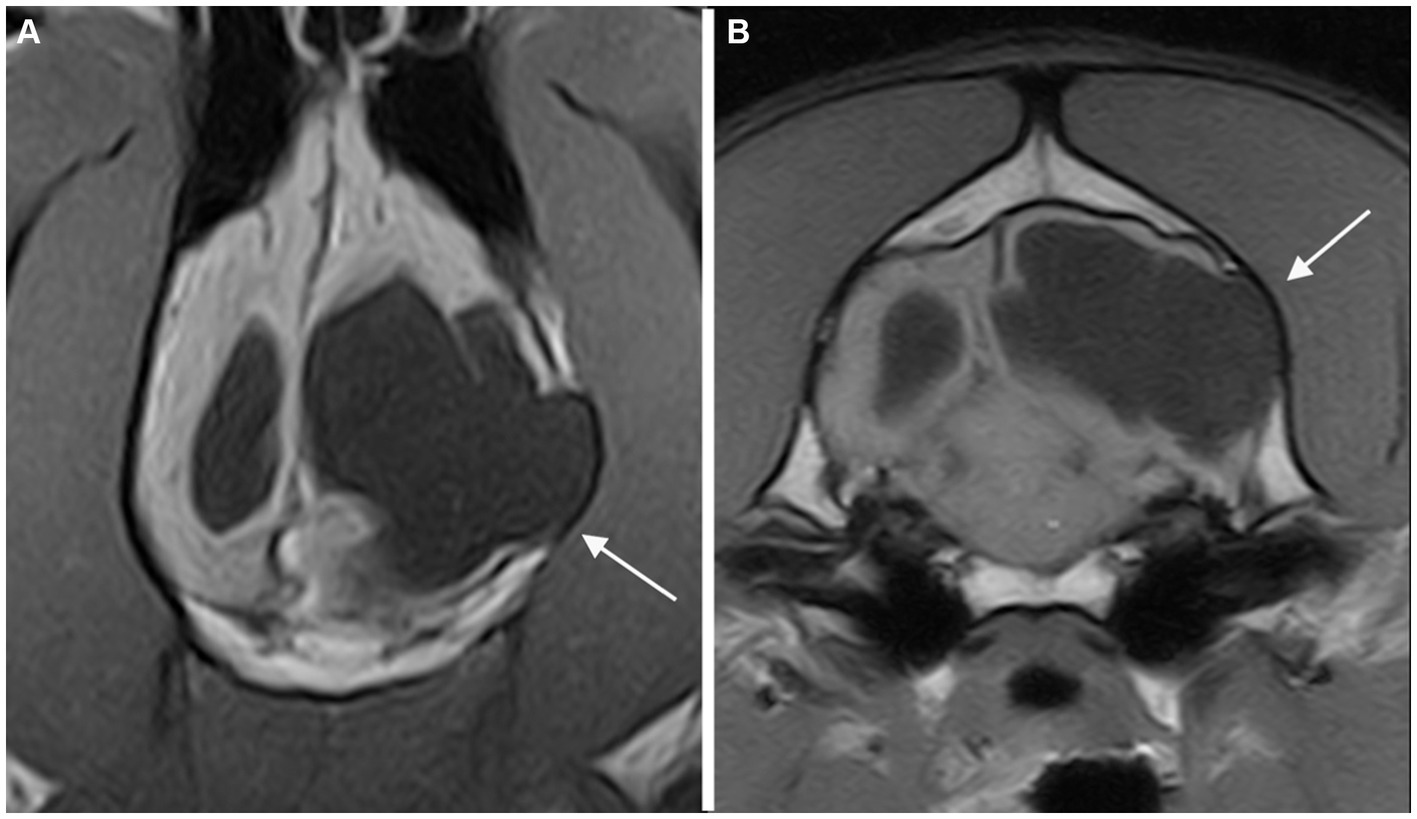

Figure 2

Dorsal T1-weighted MR-images of the brain of a dog showing a porencephalic cavity in the right temporal lobe at level of the caudal collicoli (A) and a slice below (B). A temporal bone fracture (long arrow) associated with a mild depression of the overlying calvarium is appreciated. Abnormal signal of the right temporal muscle (fat infiltration) is also present (short arrow).

All fourteen cases with fractures presented at least two further musculoskeletal changes and then were classified as presumed acquired traumatic forms (Figure 2). Thinning of the calvarium overlying the PC was seen in 3 cases (Figure 3). None of them presented further musculoskeletal abnormalities. Depression of the calvarium was seen in 13 cases, all but one of which were associated with fractures. Thirteen cases showed masticatory muscle changes, all but one of which were associated with fractures.

Musculoskeletal changes were observed in 20/32 cases. Fourteen of 20 cases showed evidence of fractures. All these abnormalities were closely related to the PCs.